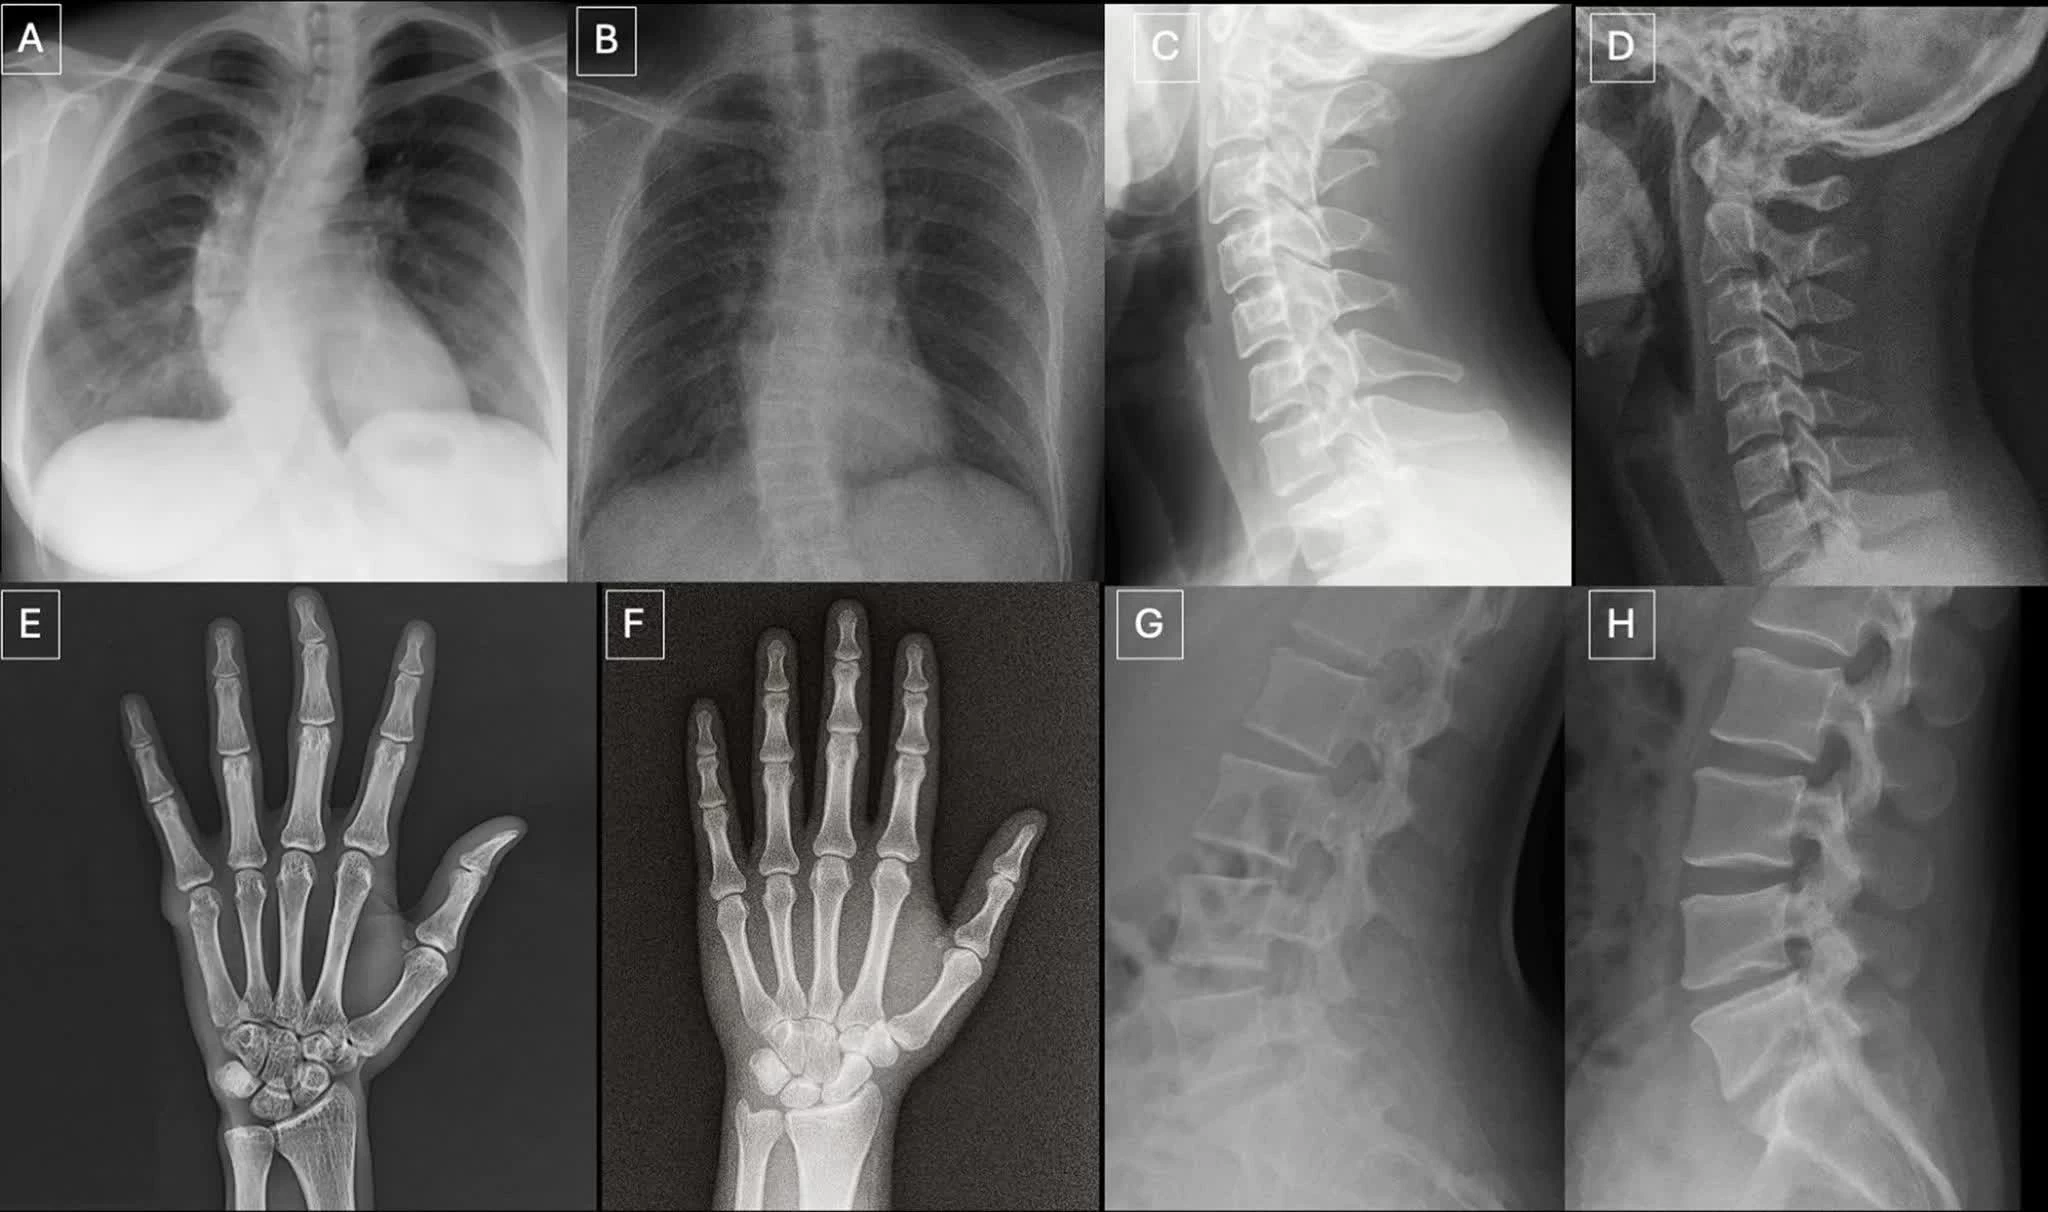

Ảnh X-quang ghép theo từng cặp gồm ảnh thật và ảnh do GPT-4o tạo ra ở các vị trí khác nhau của cơ thể, cho thấy AI có thể tạo ra hình ảnh y khoa có độ chân thực cao. Nguồn: Hiệp hội X quang Bắc Mỹ (RSNA)

Ảnh X-quang ghép theo từng cặp gồm ảnh thật và ảnh do GPT-4o tạo ra ở các vị trí khác nhau của cơ thể, cho thấy AI có thể tạo ra hình ảnh y khoa có độ chân thực cao. (Nguồn: RSNA)

Trong tổng 264 ảnh X-quang được sử dụng trong nghiên cứu, một nửa là ảnh thật và một nửa do AI tạo ra. Các bác sĩ tham gia đánh giá hai bộ dữ liệu riêng biệt, bao gồm nhiều vùng cơ thể và một bộ ảnh X-quang phổi chuyên biệt, được tạo ra bằng các mô hình AI như ChatGPT và RoentGen.

Theo nhóm nghiên cứu, ảnh X-quang giả thường mang một số đặc điểm thị giác tinh vi như cấu trúc xương quá mịn, cột sống thẳng bất thường, phổi đối xứng hoàn hảo, mạch máu phân bố đồng đều và các vết gãy có hình dạng “quá đẹp”, thường chỉ xuất hiện ở một phía của xương.